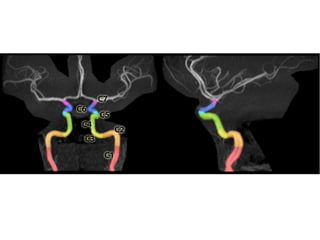

NORMAL MRA

Arteries of the brain (cranial view) - MRA

Arteries of the brain (lateral view) - MRA

7T 3D CE-MRA